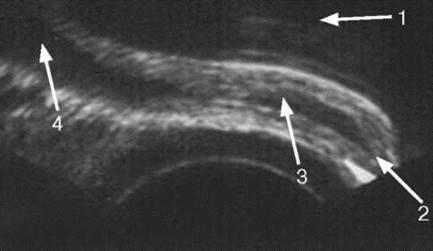

При трансректальном сканировании лучше визуализируется нижний сегмент мочевого пузыря. Пузырно-мочеточниковый сегмент представляет собой структуру, состоящую из юкставезикального, интрамурального отделов мочеточника и зоны мочевого пузыря рядом с устьем (рис. 4.18). Устье мочеточника определятся в виде щелевидного образования, несколько возвышающегося над внутренней поверхностью мочевого пузыря. При прохождении болюса мочи устье приподнимается, открывается, и струя мочи поступает в полость мочевого пузыря. По данным трансректального УЗИ можно оценивать моторную функцию пузырно-мочеточникового сегмента. Частота сокращений мочеточника в норме составляет 4-6 в минуту. При сокращении мочеточника его стенки полностью смыкаются, при этом диаметр юкставезикального отдела не превышает 3,5 мм. Сама стенка мочеточника лоцируется в виде эхоплотной однородной структуры шириной около 1,0 мм. В момент прохождения болюса мочи мочеточник расширяется и достигает 3-4 мм.

Рис. 4.17. Трансректальная сонограмма. Выброс мочи (1) из устья мочеточника (2) в мочевой пузырь (3)

Рис. 4.18. Трансректальная сонограмма пузырно-мочеточникового сегмента в норме: 1 - мочевой пузырь; 2 - устье мочеточника; 3 - интрамуральный отдел мочеточника; 4 - юкставезикальный отдел мочеточника